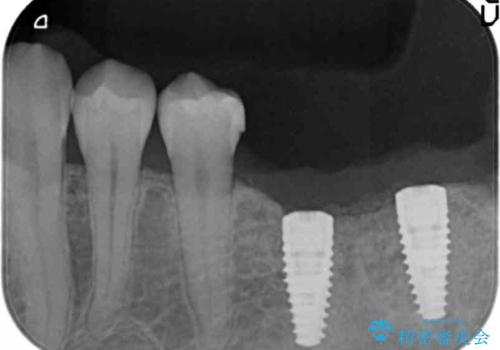

- 他院で抜歯後放置してしまった左下の奥歯の機能・見た目の回復を希望され来院されました。

放置したことによる影響か骨が吸収し、インプラント周囲に十分な骨が確保できないような状況であったため骨造成を併用したインプラント治療を計画します。

インプラントを用いて機能回復を行うことで、奥歯がしっかりと噛めるようになります。

周囲に骨があることでより長期的な予後を見込むことができます。